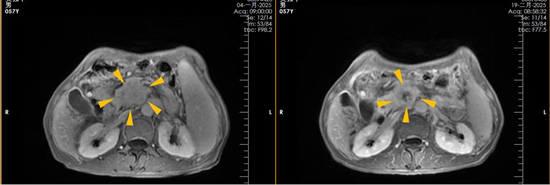

四川友谊医院肿瘤科石辉兵运用先进放疗技术实现多灶肿瘤协同治疗

近日,四川友谊医院肿瘤科石辉兵主任成功为一名同时患有鼻咽癌和早期肺癌的患者完成放射治疗、控制肿瘤进程,展现出该院在复杂多灶肿瘤综合治疗方面的技术实力与诊疗优势。